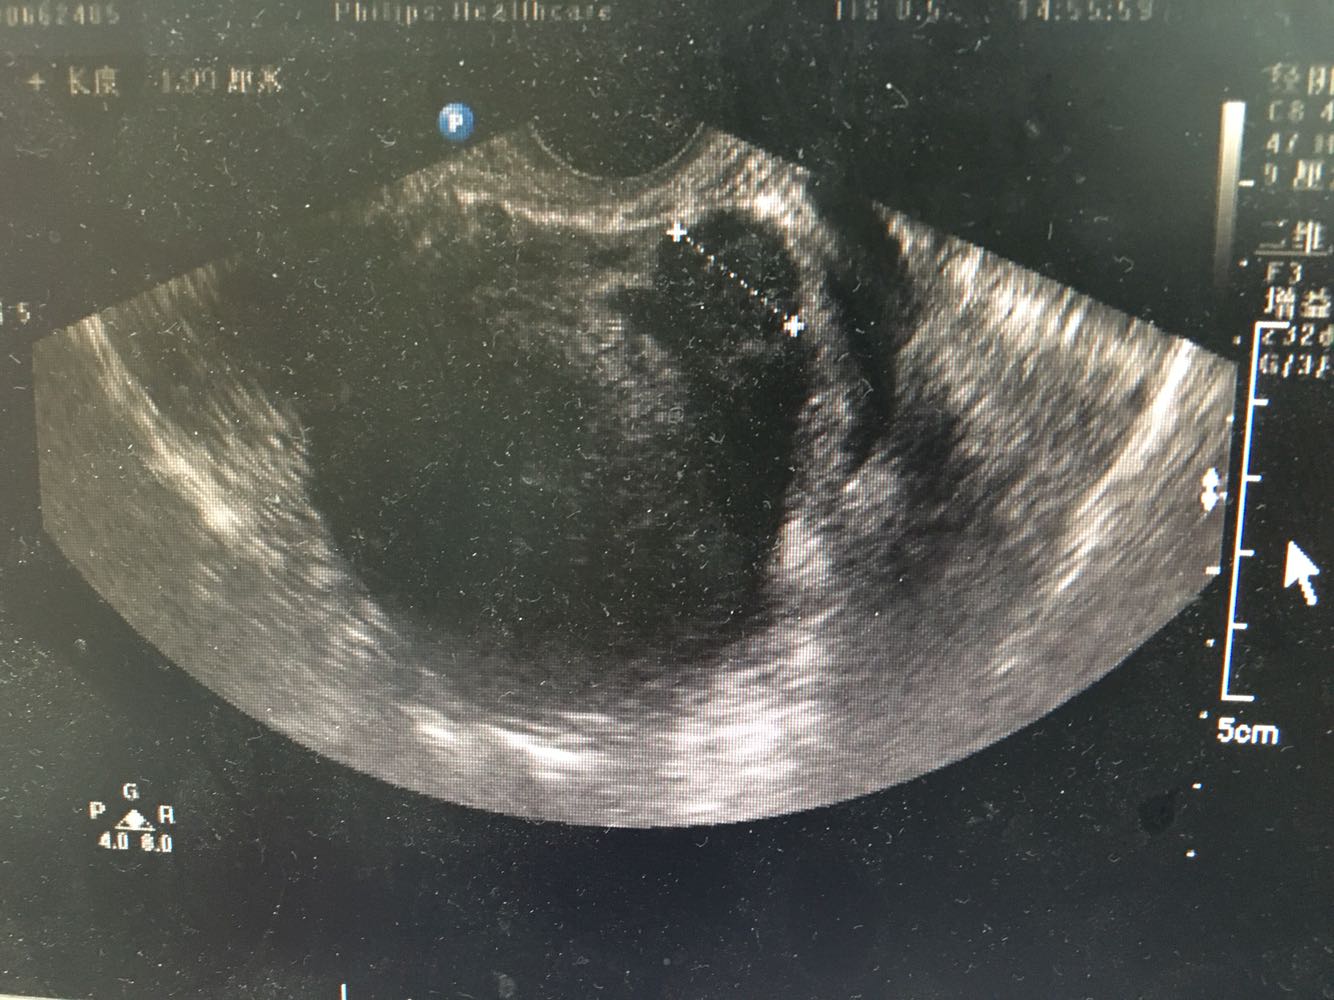

1、患者,女性,55岁 2、主诉:发现子宫肌瘤5年,伴进行性增大伴半年 现病史:1-0-2-1,初潮16岁,平时月经规律,6/28天,量中,痛经(±),LMP:2017-2-13。患者2015年体检时发现子宫肌瘤(具体报告未见),当时月经量无增多,偶伴痛经,偶伴腹胀感,无下腹疼痛感,无头晕乏力,无腰酸背痛,无异常阴道流血流液,存在白带增多伴异味,无尿频尿急。之后定期复查体检发现子宫进行性增大,半年前妇科B超:可见数个最大约67*60*56mm的低回声团块,界清,内部回声不均匀,提示子宫肌瘤,患者自觉尿频,每日小便10多次,夜间小便1次,有尿不净感,偶有腰酸、肛门坠胀感,建议患者手术治疗,为求进一步诊疗,遂就诊门诊,门诊拟“子宫肌瘤”收治。 3、既往史:妇科炎症30余年,白带量多,有异味,否认其他慢性病史

查体:外阴(-);阴道通畅;未见明显异常分泌物;宫颈光滑,正常大小,子宫后位,如孕3月大小,质中,无压痛,表面凹凸不平,附件:双侧附件(-)